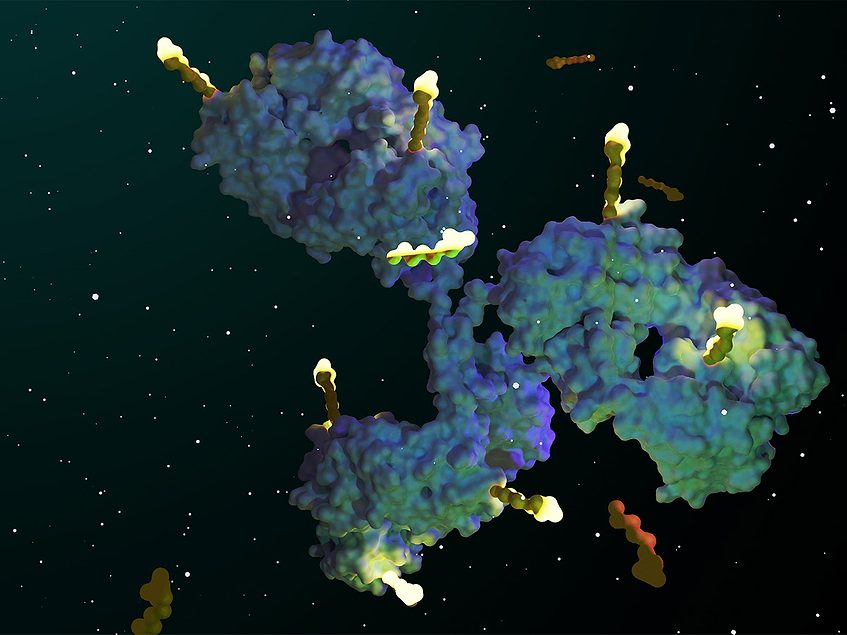

Zanidatamab Displays Safety, Efficacy in HER2-Expressing Gastric Cancer

Zanidatamab-hrii (Ziihera) with or without chemotherapy displayed a manageable safety profile and favorable efficacy outcomes in heavily pretreated patients with HER2-expressing gastroesophageal adenocarcinoma (GEA), according to results from a dose- …